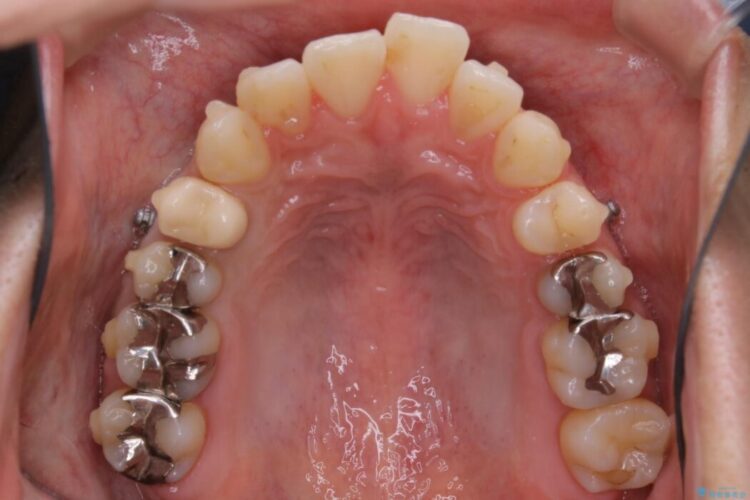

マイクロインプラントについて

本症例では上顎前突(出っ歯)や歯列のがたつきを改善するスペースを確保するために、歯を遠心移動をサポートすることができるマイクロインプラントを用いたゴムかけを行っていただきました。

それにより従来の矯正治療と比べましても効率的に歯の移動を行えるため、非抜歯の場合でも歯列を整えることが可能となります。